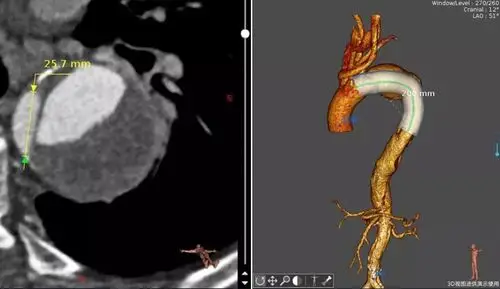

支架置入后

支架系统治疗胸主动脉夹层 ——延安大学附属医院心脏血管医学中心